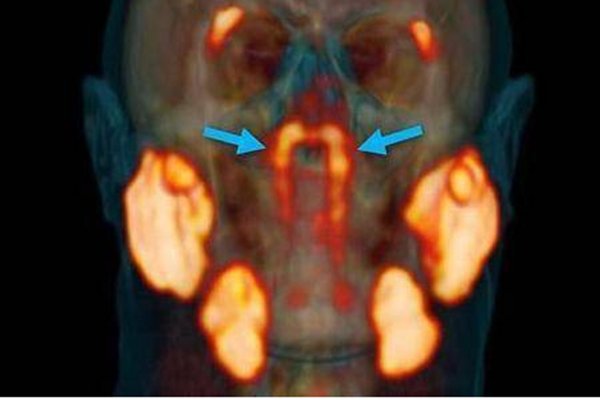

10月20日外媒报道,荷兰的一个研究癌症的研究在人体内发现了新的器官,该器官位于鼻咽里面咽鼓管隆凸的软骨上 ,据研究人员称这是一种腺体,以前人们从没有发现过。

因为其生在的部位,所以专家们给它命名为隆凸唾液腺,人类在之前只有发现了三大唾液腺分别是腮腺、颌下腺和舌下腺,现在发现这个唾液腺很可能会成为第四大,具体还需要专家们做出详细解释。

一般治疗癌症都会用到放射性治疗,但是在脖子很头部做放射性癌症治疗时,患者会在吃东西,吞咽或者说话时感到比较困难,现在看来就是因为破坏了腺体。

现在发现了这个腺体,医生在给患者做放射性癌症治疗时,就可以避免出现以前的那种情况,这对于癌症病人来说是一个非常好的消息。